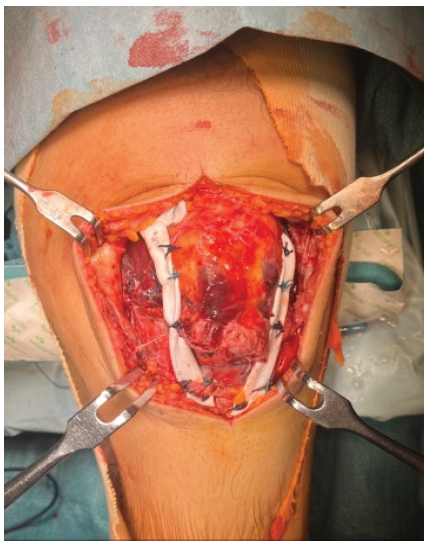

Notably, also the medial and lateral capsule was teared. First, the tendon sides were attached using non-absorbable sutures, and the anteromedial and anterolateral capsules were reconstructed using the same sutures (Fig. 3).

Figure 3: Tenorrhaphy and reconstruction of anteromedial and anterolateral capsule.

Subsequently, with the knee flexed at 30°, a tubular GORE® stretch Vascular Graft (Newark, New Jersey, US) was prepared. First, it was passed from medial to lateral into the quadriceps tendon and secondly attached with non-absorbable sutures at paratendinous sides (Fig. 4).

Figure 4: Insertion of the Gore-Tex membrane into quadriceps tendon.

The membrane was then tightened and attached at the level of the tibial tuberosity with intraosseous stitches, without the need of anchors or bone tunnels (Fig. 5).

Figure 5: Gore-Tex membrane fixation and tendon augmentation.